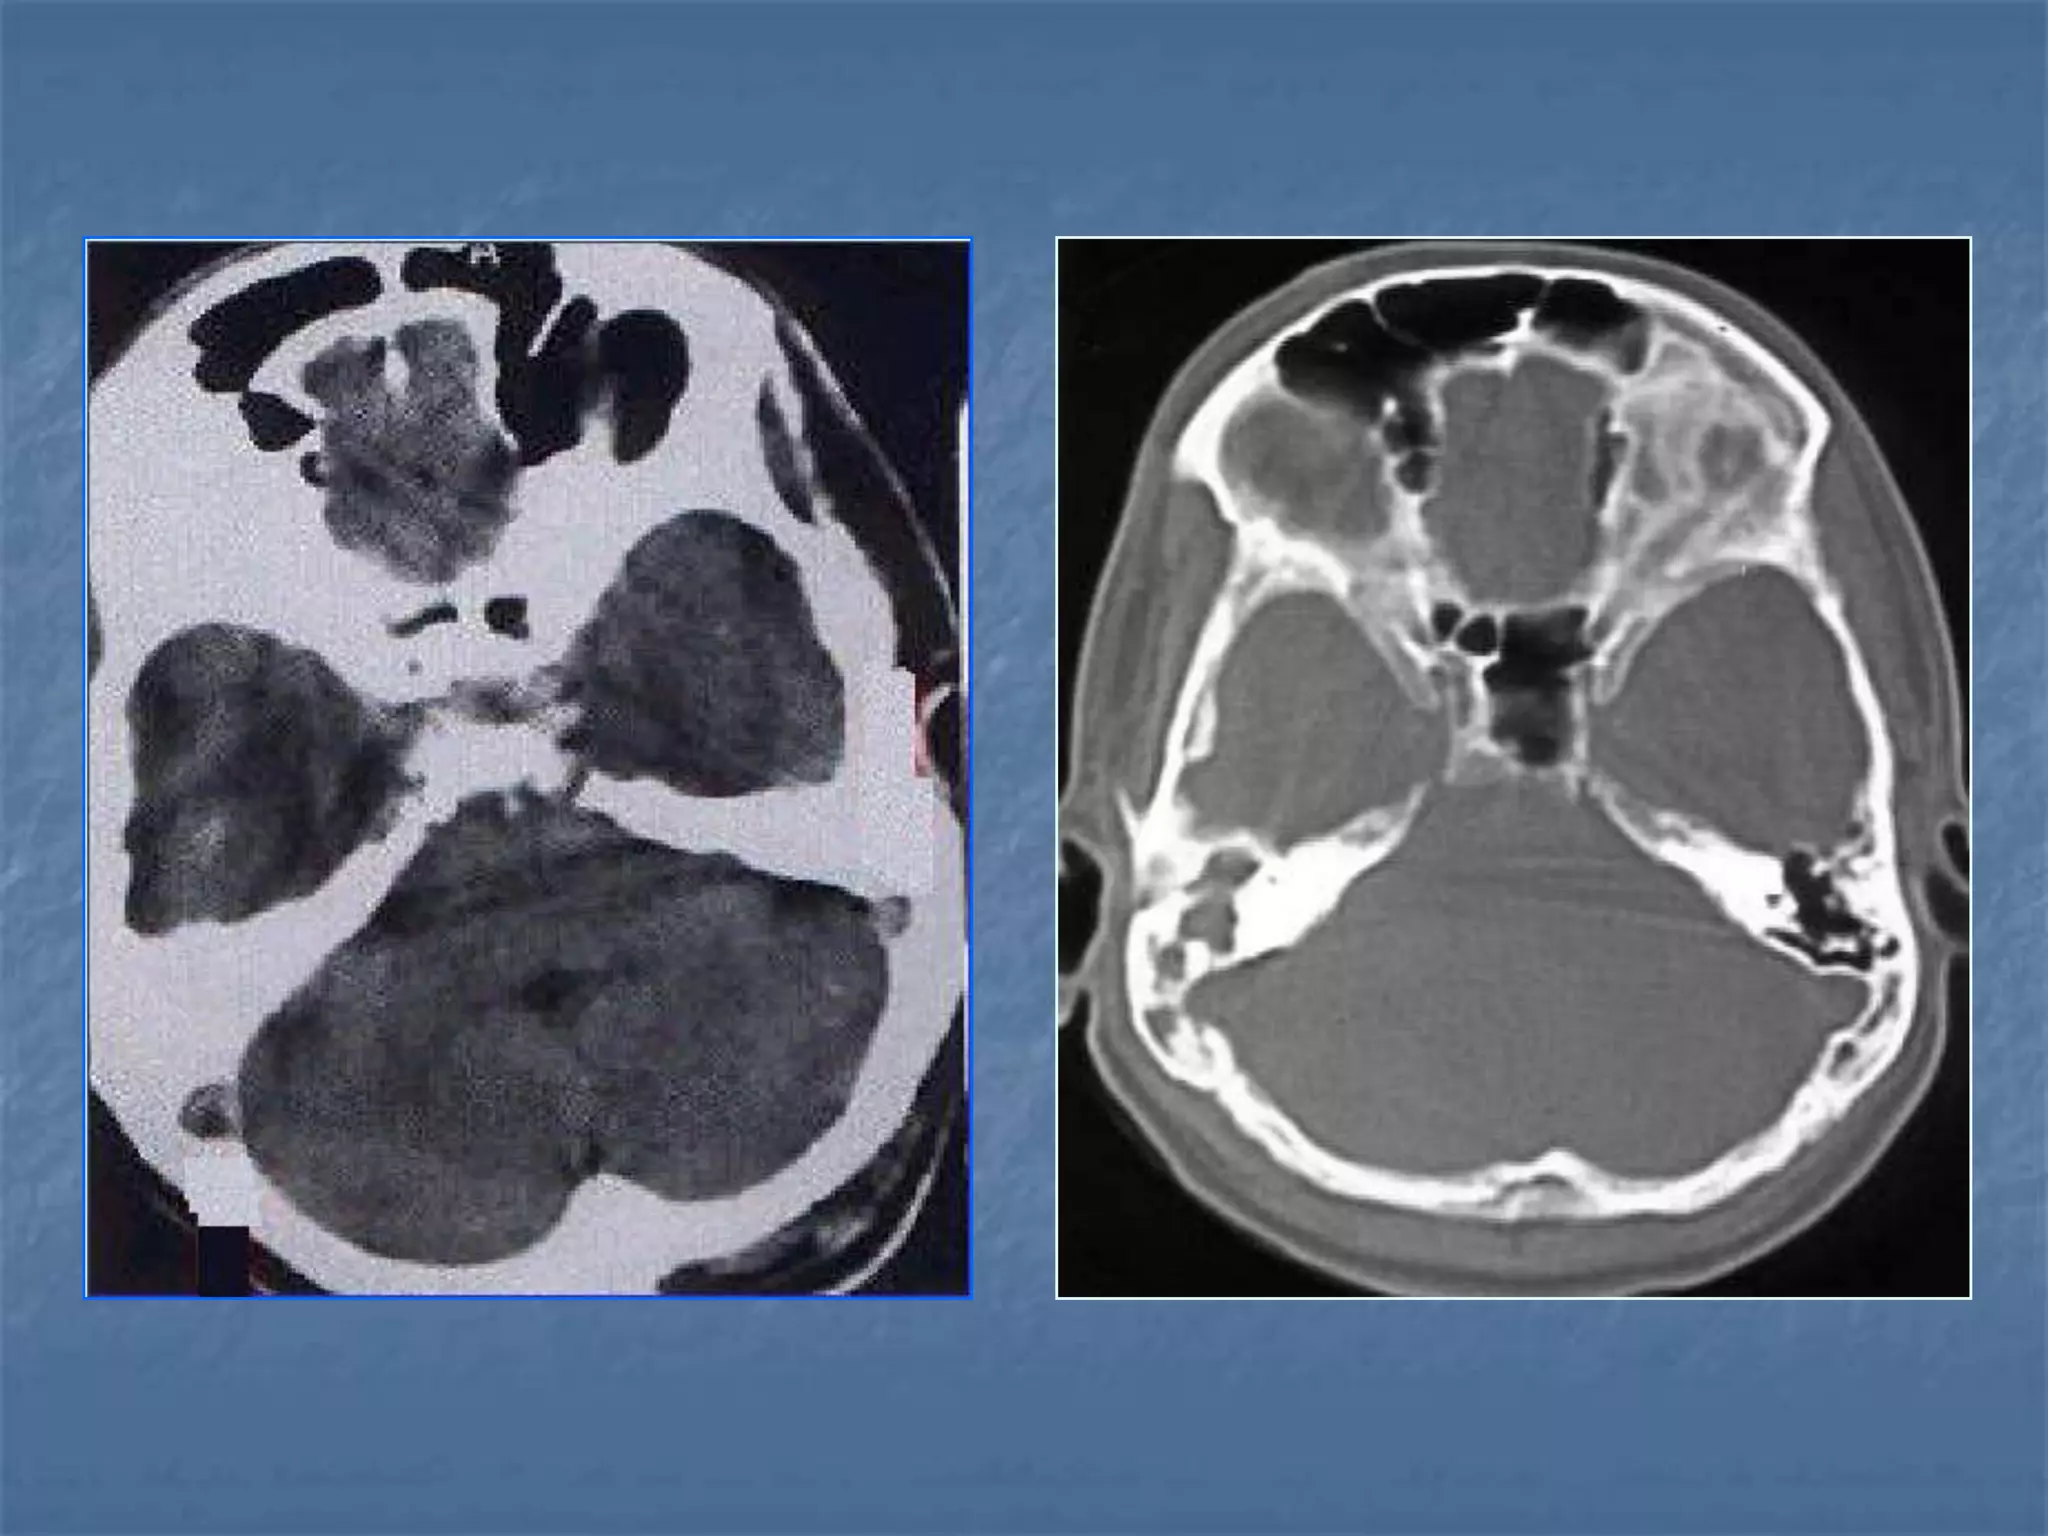

Subarachnoid hemorrhage

 In the absence of trauma, the most common cause

of subarachnoid hemorrhage is a ruptured cerebral

aneurysm. Cerebral aneurysms tend to occur at

branch points of intracranial vessels and thus are

frequently located around the Circle of Willis.

Common aneurysm locations include the anterior

and posterior communicating arteries, the middle

cerebral artery bifurcation and the tip of the basilar

artery. Subarachnoid hemorrhage typically presents

as the "worst headache of life" for the patient.

Detection of a subarachnoid hemorrhage is crucial

because the rehemorrhage rate of ruptured

aneurysms is high and rehemorrhage is often fatal.

 CT is currently the imaging modality of choice because

of its high sensitivity for the detection of subarachnoid

hemorrhage. CT is most sensitive for acute

subarachnoid hemorrhage. After a period of days to

weeks CT becomes much less sensitive as blood is

resorbed from the CSF. If there is a strong clinical

indication, LP may be warranted despite a negative CT

since small bleeds can be unapparent on imaging.

On CT, a subarachnoid hemorrhage appears as high

density within sulci and cisterns. The insular regions

and basilar cisterns should be carefully scrutinized for

subtle signs of subarachnoid hemorrhage.

Subarachnoid hemorrhage may have associated

intraventricular hemorrhage and hydrocephalus.